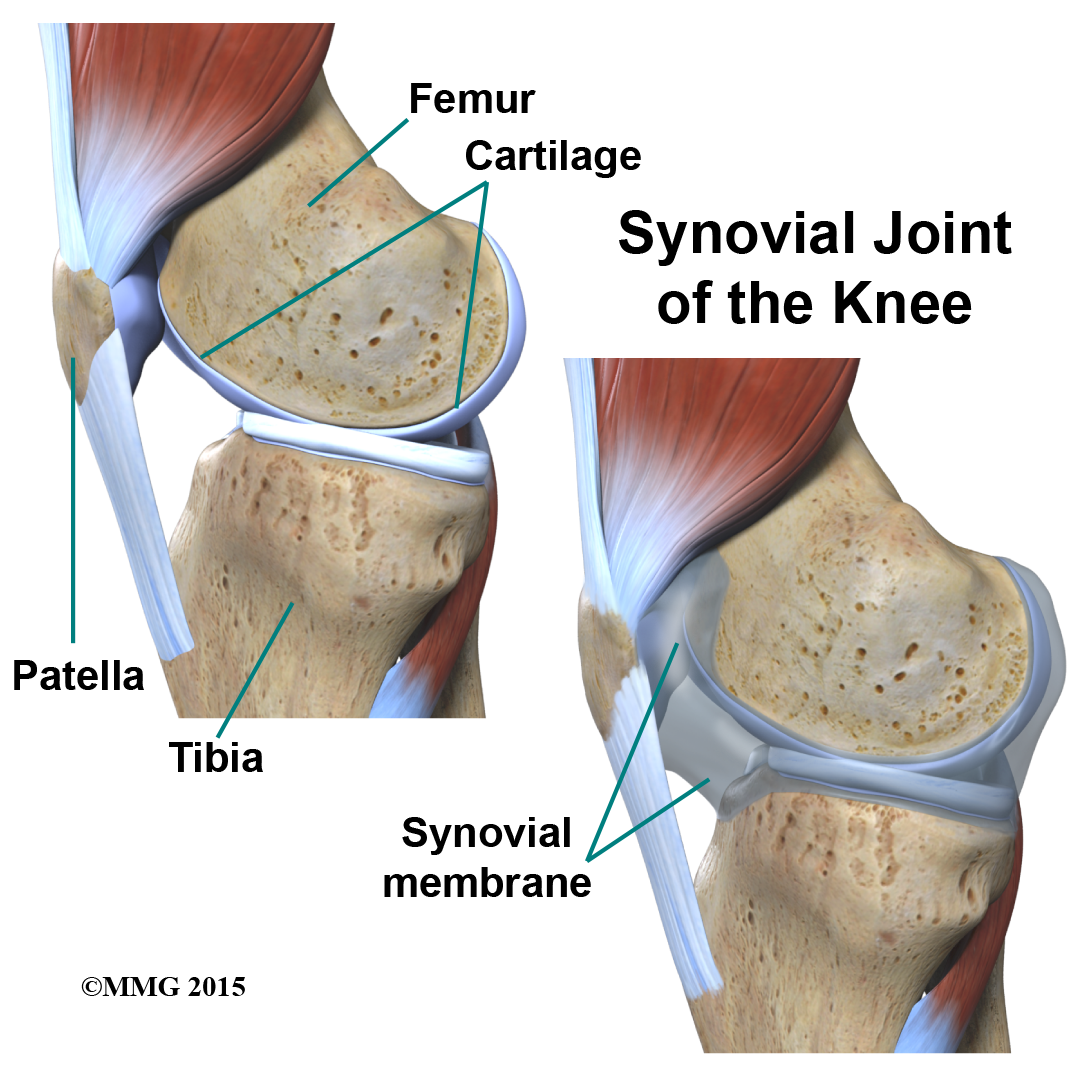

The knee joint is a synovial joint. are enclosed by a ligament capsule and contain a fluid, called synovial fluid, that lubricates the joint.

The end of the femur joins the top of the tibia to create the knee joint. Two round knobs called femoral condyles are found on the end of the femur. These condyles rest on the top surface of the tibia. This surface is called the tibial plateau. The outside half (farthest away from the other knee) is called the lateral tibial plateau, and the inside half (closest to the other knee) is called the medial tibial plateau. The patella glides through a special groove formed by the two femoral condyles called the patellofemoral groove.

is the material that covers the ends of the bones of any joint. This material is about one-quarter of an inch thick in most large joints. It is white and shiny with a rubbery consistency. Articular cartilage is a slippery substance that allows the surfaces to slide against one another without damage to either surface. The function of articular cartilage is to absorb shock and provide an extremely smooth surface to facilitate motion. We have articular cartilage essentially everywhere that two bony surfaces move against one another, or articulate. In the knee, articular cartilage covers the ends of the femur, the top of the tibia, and the back of the patella.